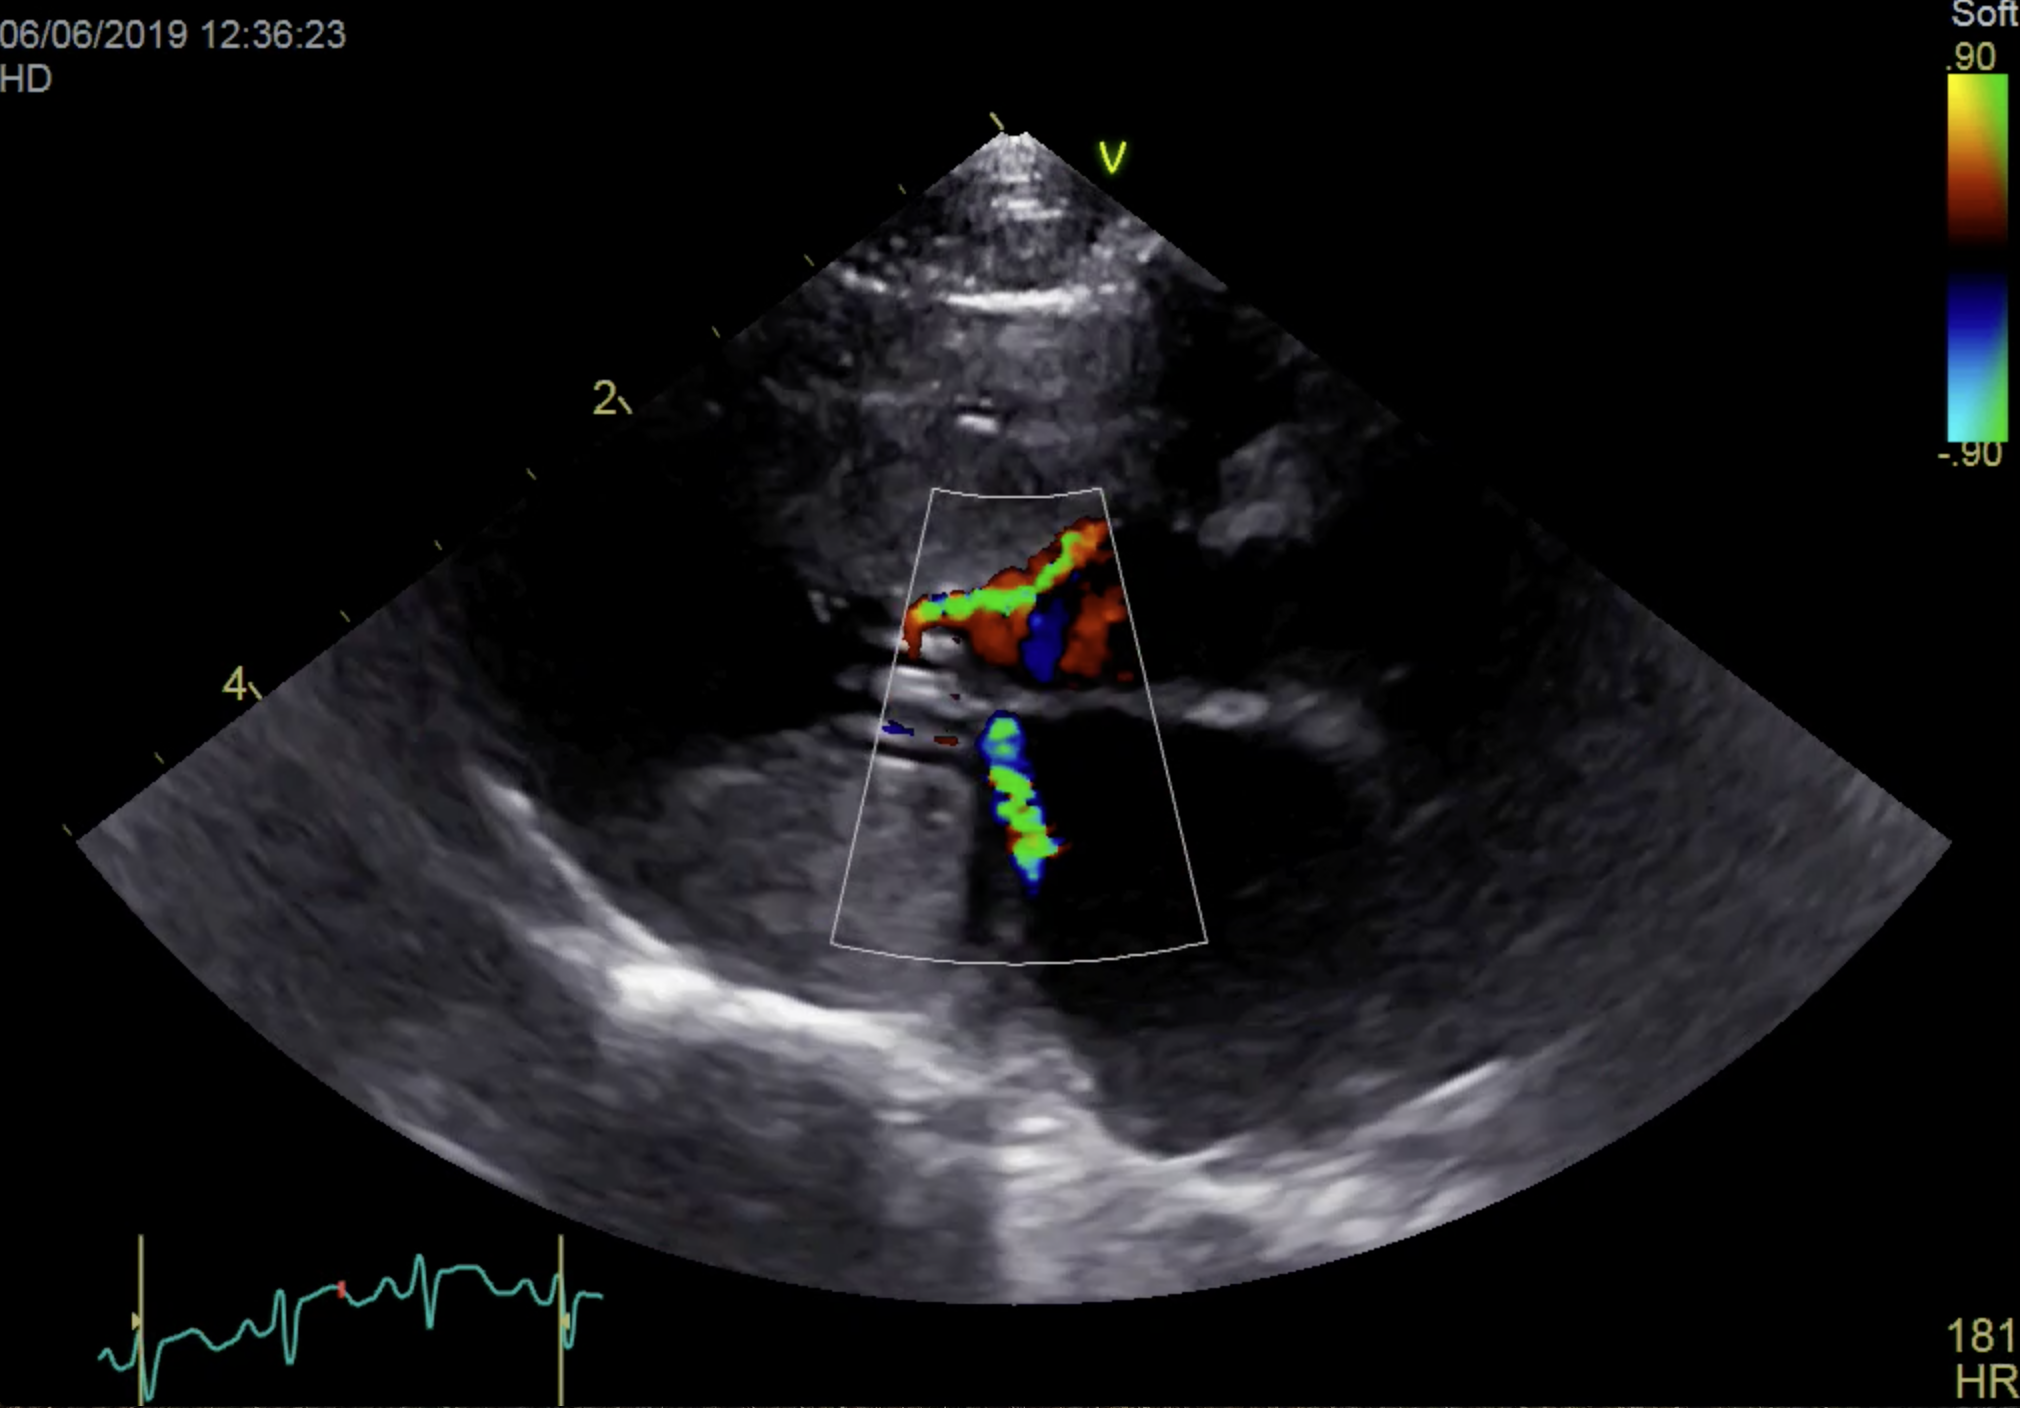

• Exploiter pleinement l’examen clinique et les examens complémentaires (échocardiographie, radiologie, ECG)

• Acquérir des images échocardiographiques de qualité lors des travaux pratiques

• Réaliser les mesures classiques de taille et de fonction cardiaque sur des images de patients félins

• Session pratique : interprétation et mesures sur images préenregistrées